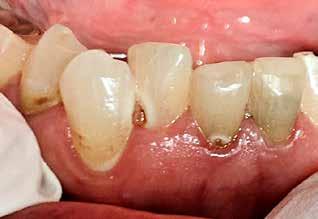

Cervikal caries

Fig. 2. Øget cariesaktivitet hos en 69-årig kvinde som følge af lægemiddelindu ceret hyposalivation.

Fig. 2. Increased caries activity in a 69-year old woman due to medicationinduced hyposalivation.

ekstraheret for mange år siden. Der er ældre sufficiente metal keramikkroner på flere molarer og enkelte sufficiente sølvamal gamfyldninger i præmolarer. Desuden ses nyere plastfyldninger på facialflader på bl.a. præmolarer og incisalt på underkæbein cisiver. Der ses flere aktive carieslæsioner og generelt moderate mængder plak langs margo gingivae (Fig. 2). Gingiva fremstår moderat inflammeret, men uden patologiske pocher.